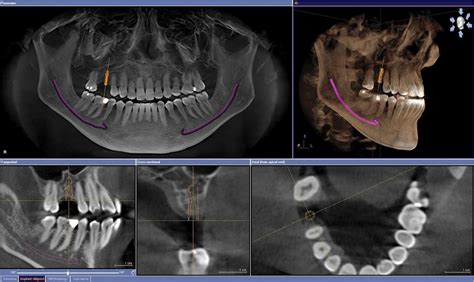

El CBCT o TAC dental es el último avance tecnológico en el campo de la radiografía dental. La tomografía computarizada dental de haz cónico (TC) es un equipo de rayos X que se utiliza en la odontología sobre todo en las áreas de implantología, cirugía maxilofacial, endodoncia y ortodoncia. Su principal diferencia respecto a las radiografías convencionales es, precisamente, su capacidad para obtener imágenes en 3D, lo que nos permite contar con una visión más completa y detallada de la anatomía dental y ósea de una persona. Se diferencia de una ortopantomografía en que la imagen es en 3D en vez de 2D dando mayor información espacial, lo que nos da datos mucho más útiles a la hora de hacer un buen diagnóstico.

El TAC dental capta centenares de imágenes de todas las estructuras anatómicas de la boca: músculos, huesos, vasos sanguíneos y nervios. Desde el monitor, el odontólogo podrá estudiar en detalle la imagen final para establecer el diagnóstico del paciente y determinar el tratamiento a seguir.

- Planificación de implantes dentales: El TAC 3D es invaluable para la planificación de implantes dentales. Permite medir con precisión el volumen y densidad del hueso disponible para garantizar una colocación adecuada del implante. Gracias a la precisión que ofrece el TAC dental, un implantólogo puede planificar con todo detalle la operación. El TAC es imprescindible antes de la colocación de implantes dentales. Se usa durante la fase de estudio para observar y analizar las estructuras óseas del paciente. El TAC dental nos da la opción de colocar “virtualmente” los implantes gracias a los diferentes software que existen. Esto nos asegura que a la hora de la intervención el cirujano sepa con mucha seguridad cual es lugar más apropiado. También nos facilita que en intervenciones más complejas la tasa de éxito aumente. El CBCT permite identificar la mejor vía para el acceso quirúrgico. Reduciendo así el riesgo de lesiones neurológicas, dentales. La prueba diagnóstica permite que se pueda estudiar la estructura ósea y así averiguar la posición exacta para colocar el implante en el hueso. El dentista podrá hacer en el ordenador cortes bi y tridimensionales de las imágenes que obtiene.